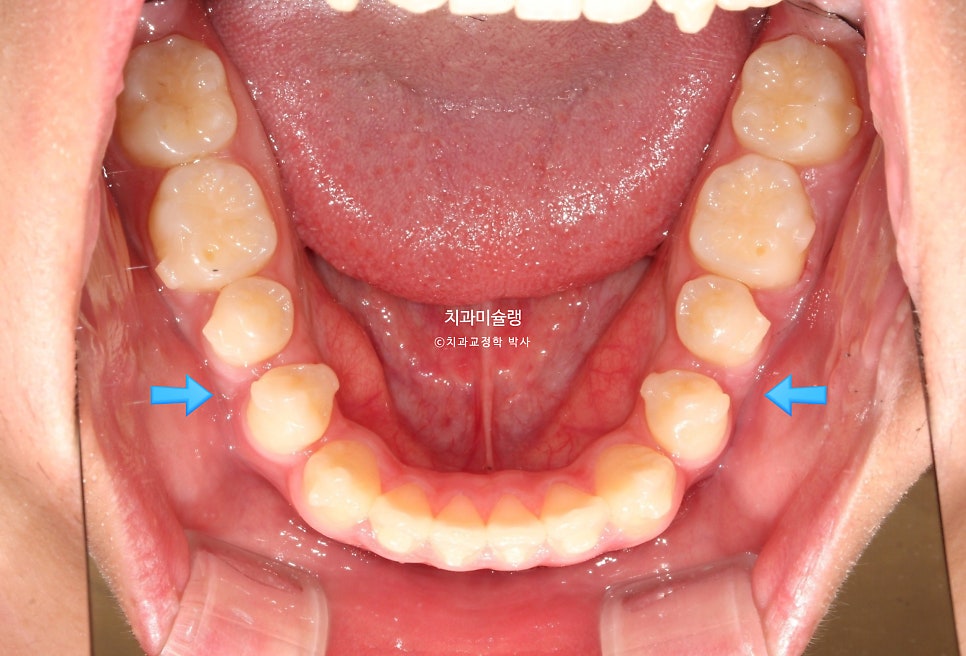

첫 세트 장치는 총 50개가 나왔습니다. 환자분은 장치를 들고 출국했다가 2025년 봄방학때 잠깐 들어와 중간 체크를 하고 다시 출국, 4달후 여름방학을 맞아 내원했을때 25번 장치를 끼고있던 모습입니다.

교정용 나사와 뺏다꼈다 하는 고무줄로 아래 어금니 후방이동을 도모하는 중입니다.

파란 화살표에 공간이 생긴만큼 어금니가 사랑니 공간으로 잘 이동했습니다.